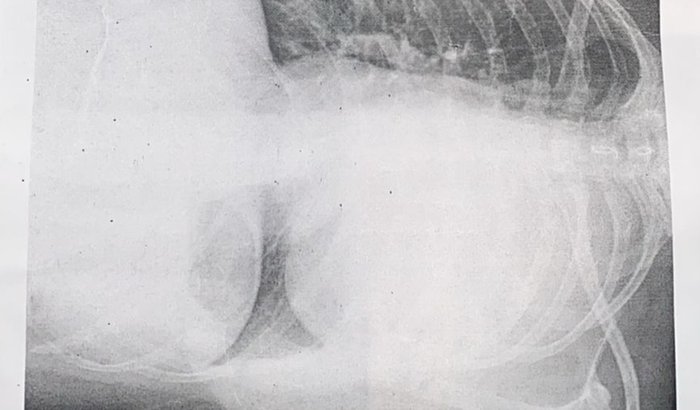

Meu nome é Yasmim ferreira, 23 anos, e aparentemente era uma menina saudável que não bebe, não fumou. Início desse ano fiquei internada porque acharam que eu estava com pneumonia e fiz o tratamento mas não era, o meu pulmão esquerdo está todo tomado por um tipo de massa que ninguém sabe oque é ainda, porém os médicos disseram que eu teria que fazer uma cirurgia torácica e tirar um pedaço da massa pra investigar se é benigno ou maligno. Esse procedimento é urgente porque como não sabemos oque é precisamos de tempo pra tratar, mas estou dependendo do sus, estou na fila do sisreg desde abril e nada de sair, eu não tenho plano de saúde e estou sem condições agora nem pra pagar consulta particular, então peço quem puder me ajudar, pois já não estou tendo mais qualidade de vida, qualquer coisa que eu faço eu me sinto muito cansada e fadigada, fora a falta de ar que aparece a todo o momento. Então se eu puder fazer no particular como não sai a vaga no sisreg vai me ajudar muito, a saber oque eu tenho logo e poder tratar pra poder voltar minha vida ao normal, Deus abençoe!